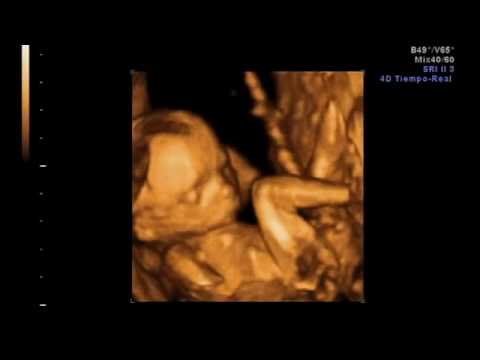

Cuando una mujer está embarazada no dice: “Llevo dentro un tumor”, sino que dice: “Estoy esperando a un niño”. Podrá esperarlo con más ilusión o con menos, pero que espera un niño lo sabe ella y los sabemos todos. Máxime desde que el álbum familiar comienza no con las fotos del recién nacido, sino con las ecografías del mismo.